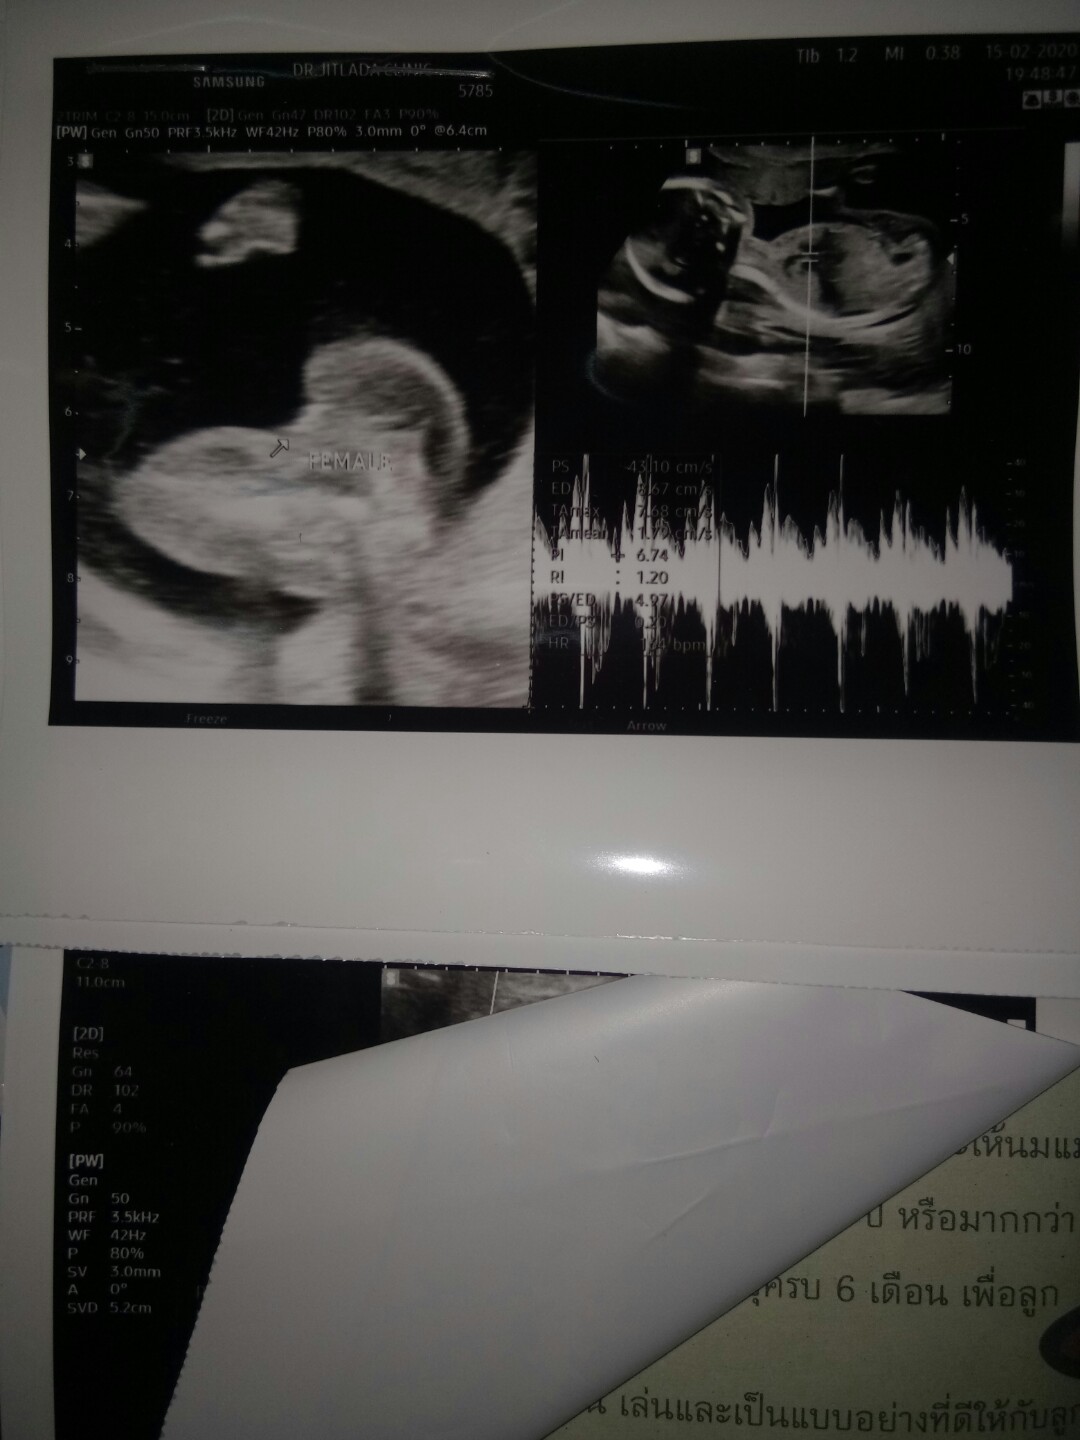

20ก.ค จร้า ได้หญิงจร้า